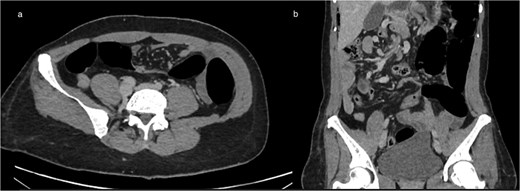

(a) Axial CT showing marked colonic distension upstream with an abrupt transition point in the right abdomen, consistent with mechanical obstruction related to volvulus (b) coronal CT reconstruction demonstrating colonic dilation and the corresponding transition zone.